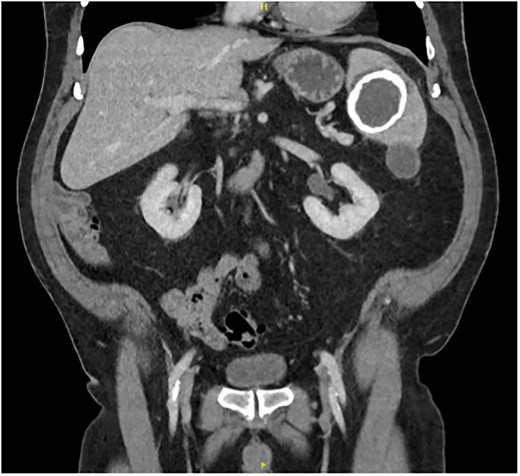

A 67-year-old gentleman was referred for management of a symptomatic, large splenic cystic lesion that had been found incidentally on coronary angiography in 2012. He had been worked up by his general practitioner at the time with a computed tomography (CT) scan which demonstrated a large, well-defined calcified splenic cyst measuring 8 cm in size (Fig. 1) and negative hydatid serology. On serial imaging over the following decade, the lesion was found to be mostly stable in size and was therefore only referred to a surgeon for definitive management in 2024 due to new symptoms of left upper quadrant (LUQ) abdominal pain and refractory nausea. This was accompanied by early satiety and unintentional weight loss of 10 kg over the preceding year. He had a medical history significant for coronary artery disease, dyslipidaemia, benign prostatic hyperplasia, and chronic obstructive pulmonary disease, and a surgical history significant for open epigastric, umbilical, and bilateral inguinal hernia repairs.

Coronal portal venous phase CT scan of the abdomen and pelvis demonstrating the calcified splenic lesion.